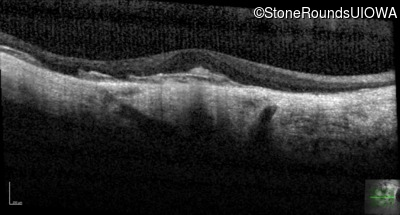

Optical Coherence Tomography - Left - 20/25 -2

Exemplar / OCT Stack

OCT Stack